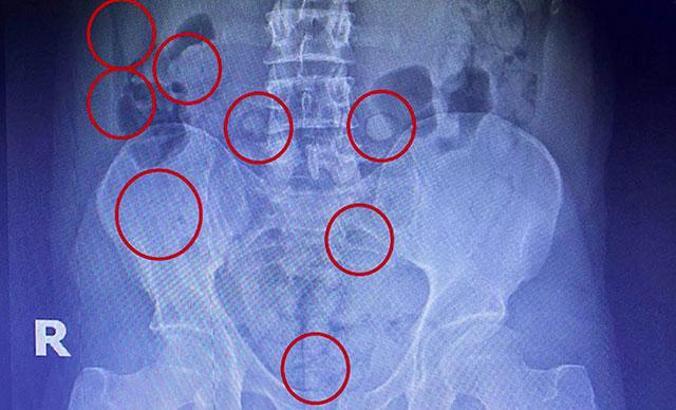

Muş Emniyet Müdürlüğü Narkotik Suçlarla Mücadele Şube Müdürlüğü görevlilerince uyuşturucu kaçakçılığı şüphesiyle İran uyruklu bir kişinin kaldığı otel odasına operasyon düzenlendi. Otel odasında 9 adet kapsül halinde daralı ağırlığı 195 gram olan metamfetamin maddesi ele geçiren polis, hareketlerinden şüphelendiği kişiyi Muş Devlet Hastanesi'nde muayeneye götürdü. Yapılan röntgen çekimlerinde İran uyruklu şüphelinin mide ve bağırsaklarında yabancı cisimler olduğu tespit edildi. Zanlının midesinden 45 adet kapsül içerisinde 305 gram, bağırsarklarından ise 54 kapsül halinde 400 gram metamfetamin maddesi çıkarıldı. Hastanede tedavisi tamamlanan şüpheli çıkarıldığı adliyede tutuklandı.